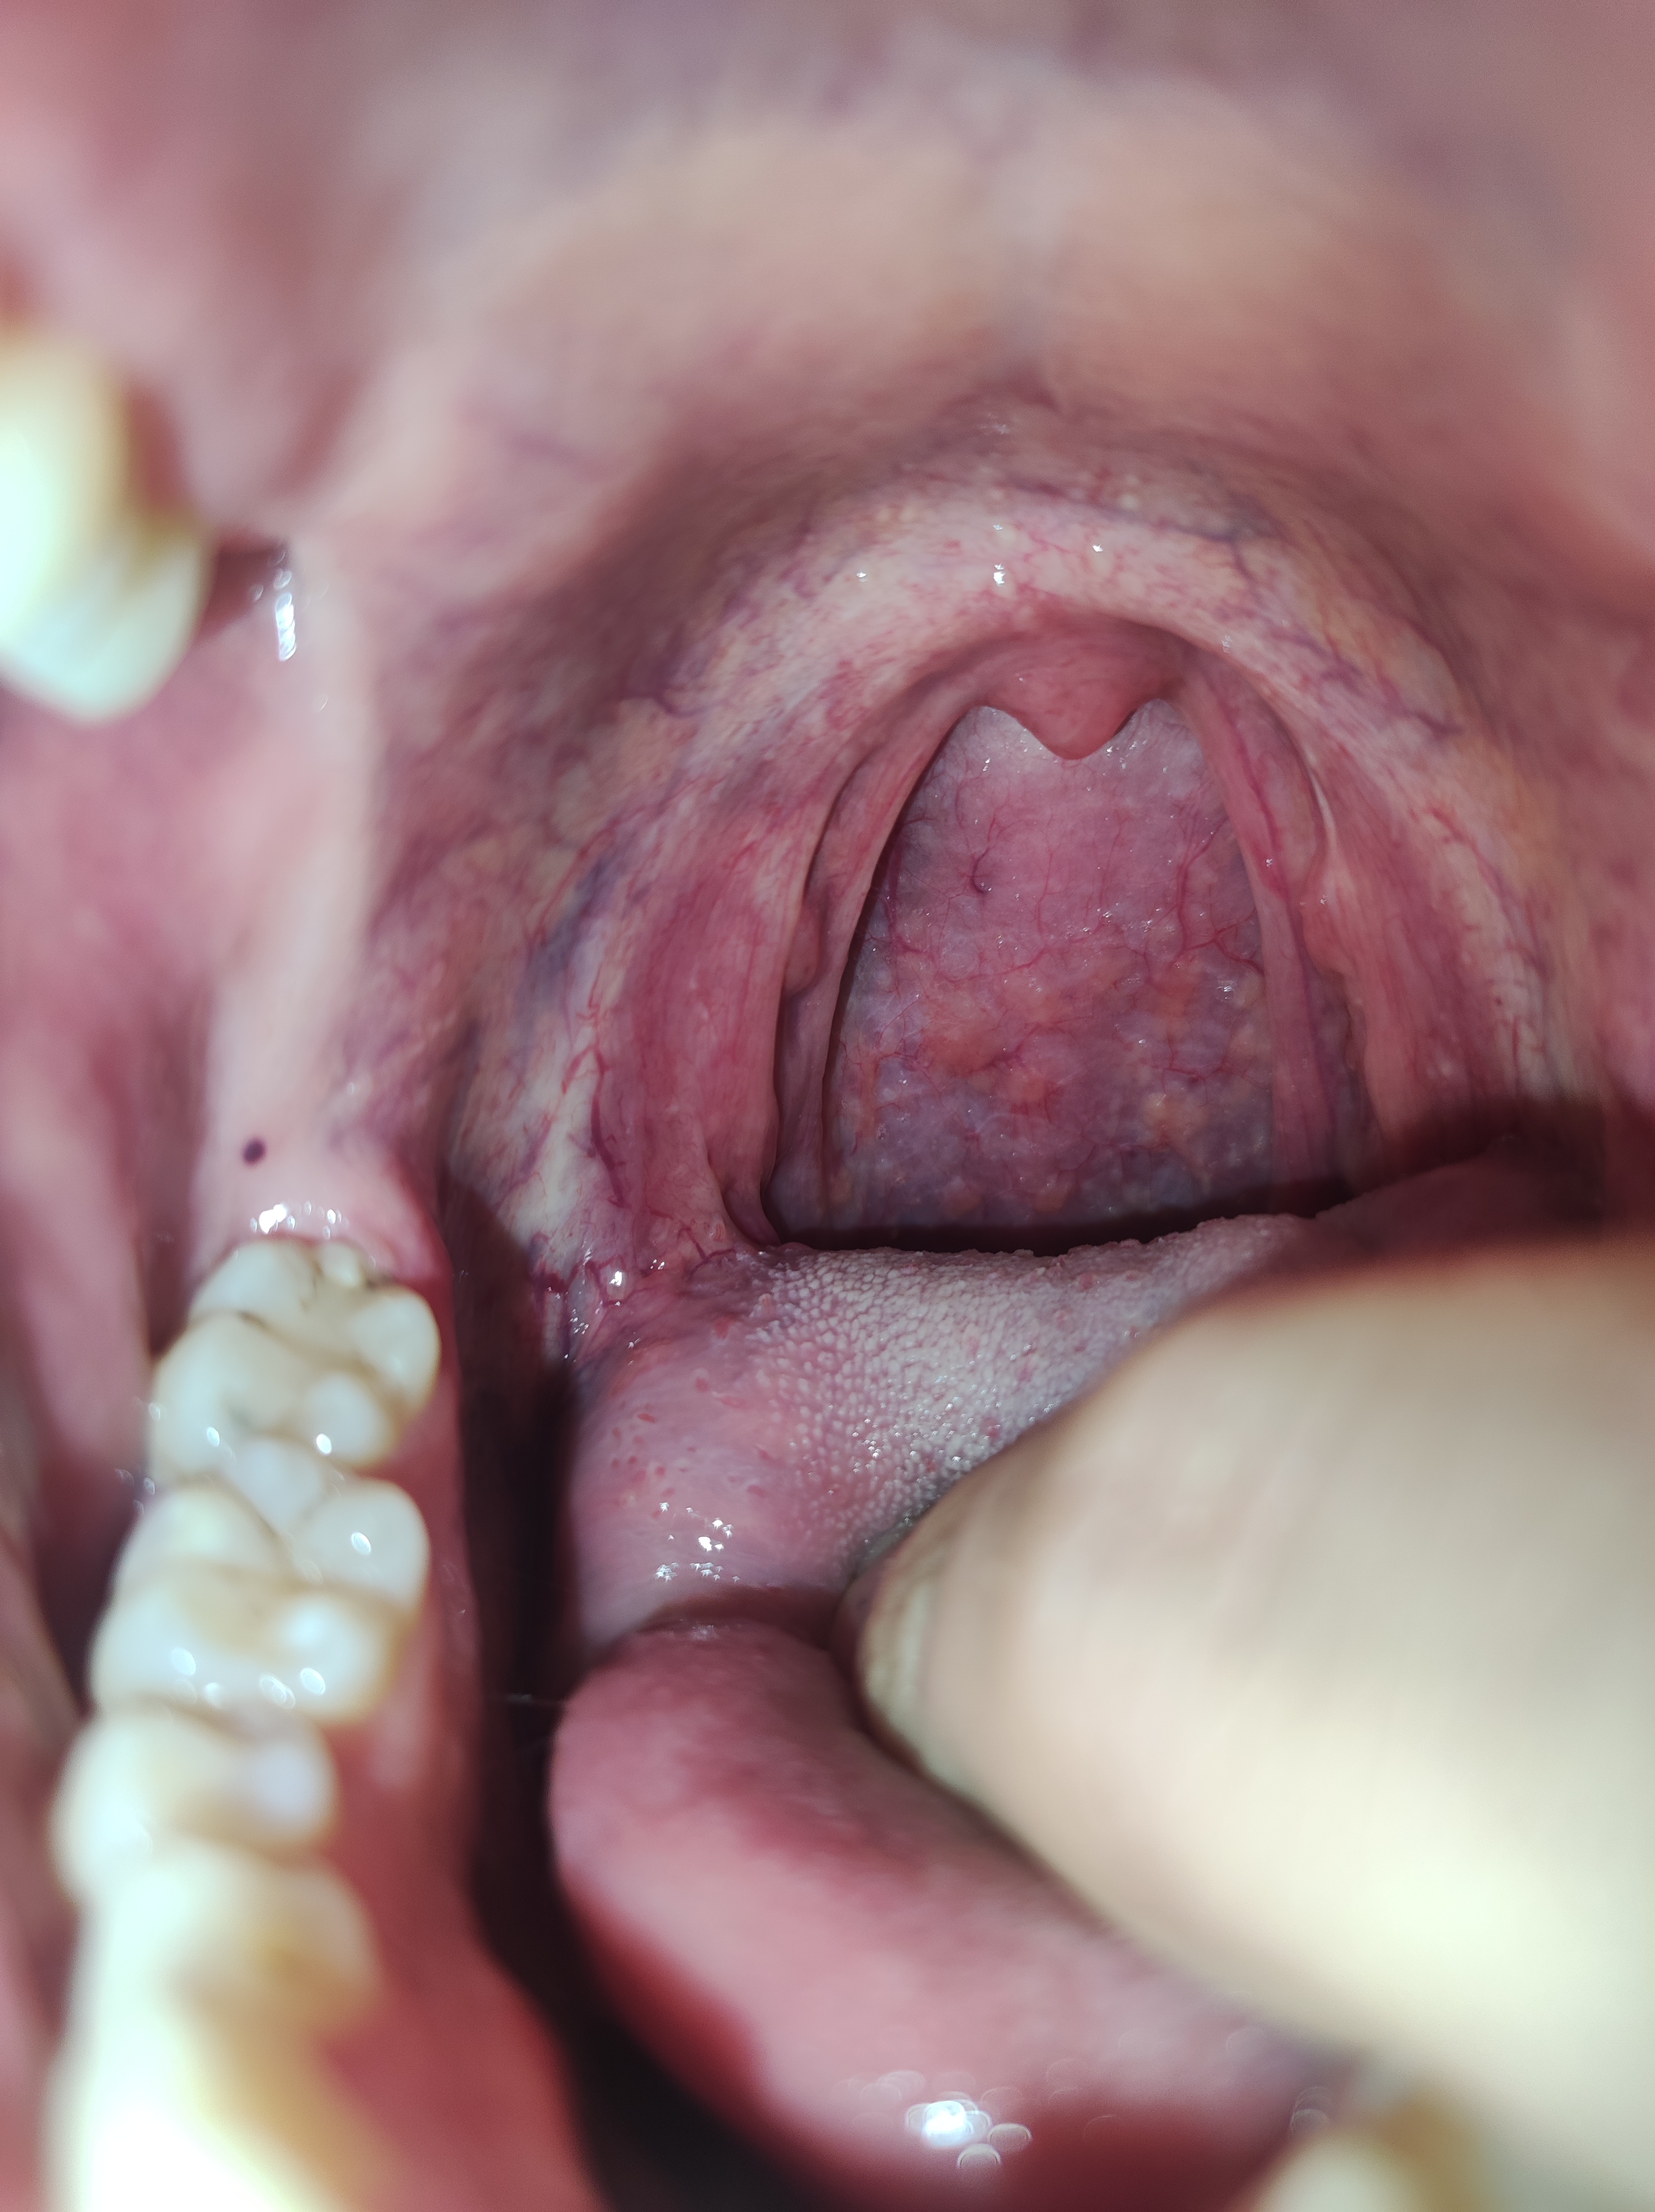

mir ist in den letzten 2 Wochen aufgefallen das dich meine Mundschleimhaut dezent verändert hat und ich immer öfters so kleine rote Blutblasen im Mund habe. Können sie mir sagen ob so etwas normal ist oder wäre es empfehlenswert einen Arzt aufzusuchen.